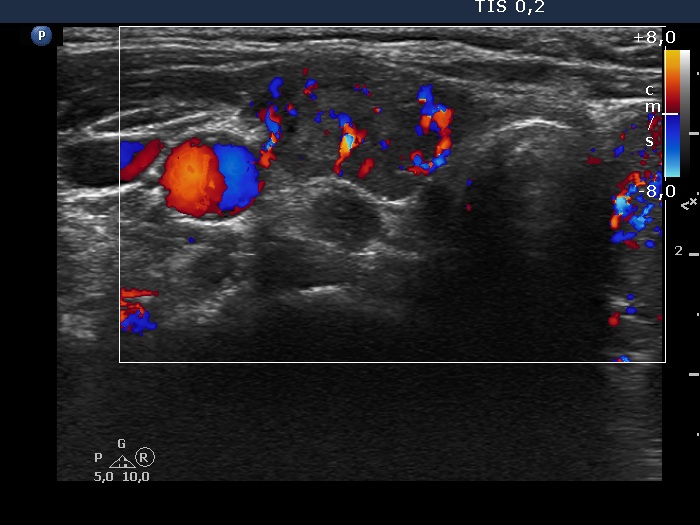

Right lobe, transverse scan, color Doppler mode. The vascularization is increased.